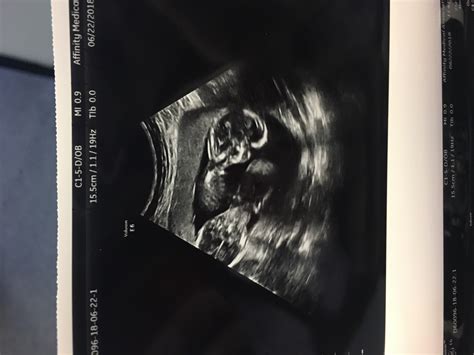

Pregnancy is an exciting journey filled with milestones, and one of the most anticipated moments is the 15 week sonogram. This ultrasound scan provides valuable insights into the development of the fetus and offers parents a glimpse into their baby's world. Understanding what to expect during a 15 week sonogram can help alleviate anxiety and enhance the overall experience.

A 15 week sonogram is an ultrasound examination performed around the 15th week of pregnancy. It is typically part of the second-trimester ultrasound, which is often scheduled between 18 and 22 weeks. However, some healthcare providers may perform an earlier scan to check on the baby’s development and ensure everything is progressing smoothly.

• Size and Appearance: The baby is about the size of an apple, measuring approximately 4 inches (10.1 cm) in length and weighing around 2.5 ounces (70 grams).

• Organ Development: The baby’s organs are developing rapidly. The liver produces red blood cells, and the pancreas is forming. The baby’s heart beats strongly, and the lungs are starting to form.

• Movement: The baby becomes more active, with increased kicking, punching, and rolling movements. Although these movements are not yet felt by the mother, they can be seen during the ultrasound.

• Fetal Measurements: The baby’s measurements, including the head circumference, abdominal circumference, and femur length, will be recorded to ensure the baby is growing at a normal rate.

• Anatomical Structures: The scan will check for the presence and proper development of all major organs and structures, such as the heart, brain, kidneys, and spine.